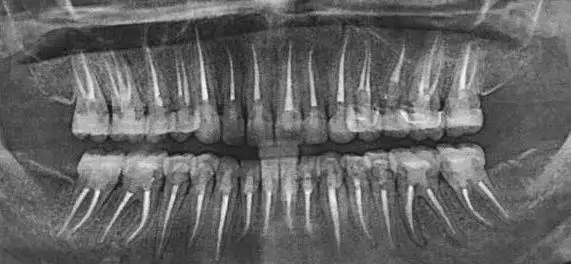

根管治疗作为口腔科最基础的治疗方法,可以缓解因为牙髓炎而导致的剧烈牙痛,操作过程中表面上看只是补了一个牙,实际上牙医做的事情远比补牙复杂!

根管治疗是每位牙医的基本功,但不是所有牙医都棒棒哒!显微镜下根管治疗,不仅仅是准确、微创更是一位口腔医生专业过硬的医疗技术体现。